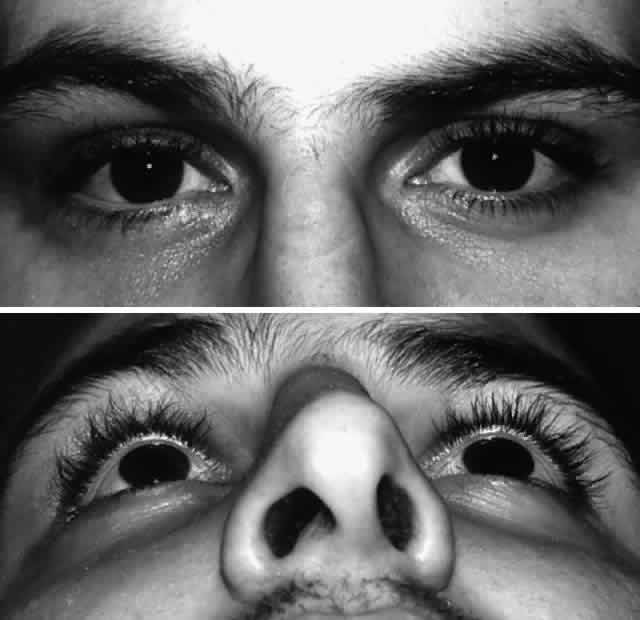

Fig. 10. A. Postoperative appearance of patient in Figure 8 showing excellent position of the globe and eyelid. B. Normal malar contour has been re-established. Fig. 10. A. Postoperative appearance of patient in Figure 8 showing excellent position of the globe and eyelid. B. Normal malar contour has been re-established.

|